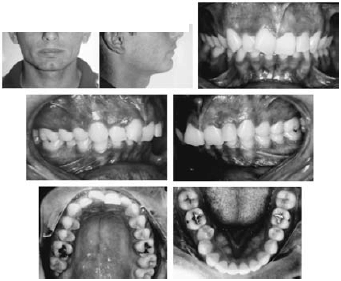

- discrepância de modelo do arco inferior: -4,00 mm

- discrepância de modelo do arco superior: -9,00 mm

| grandezas | norma | paciente |

| SNA | 82º | 80º |

| SNB | 80º | 74º |

| ANB | 2º | 6º |

| WITS | -1 mm | +8 mm |

| SNGoGn | 32º | 24º |

| FMA | 25º | 22º |

| ENAENP.GoMe | 25º | 14º |

| 1.NA | 22º | 19º |

| 1-NA | 4 mm | 2 mm |

| 1.NB | 25º | 27º |

| 1-NB | 4 mm | 4 mm |

| Pog-NB | 2,5 mm | 3 mm |

| FMIA | 68º | 56º |

| IMPA | 87º | 107º |

| H.NB | 12º | 13º |

| H-Nariz | 9-11 mm | 6 mm |

| ângulo nasolabial | 110º | 127º |

| S-Go × 100% / N-Me | 62% a 65% | 71% |